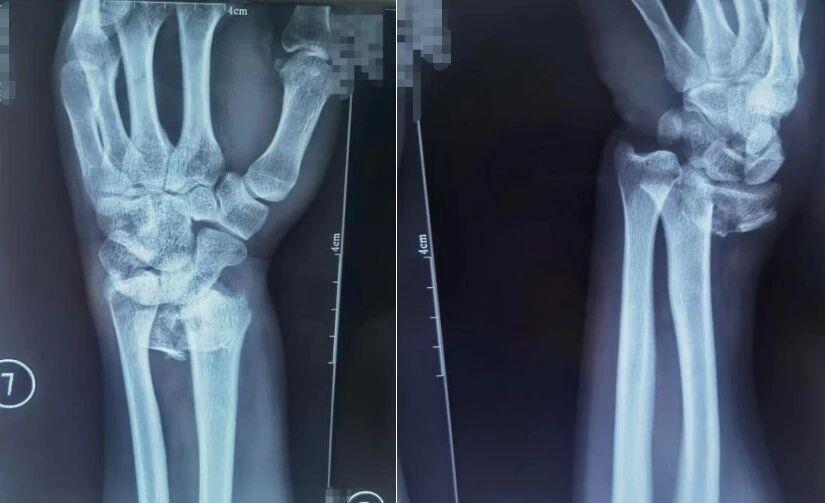

桡骨远端骨折

跌倒时用手腕撑地是常见的自我保护动作,但这一动作极易导致桡骨远端骨折,表现为手腕肿胀疼痛、活动障碍,严重时还会出现明显畸形。

△患者桡骨远端骨折,图为复位前正位、复位前侧位。图源:哈尔滨骨伤科医院